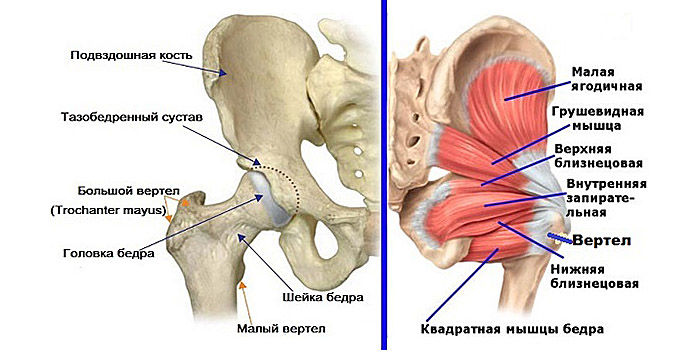

Здоровье суставов: Трохантерит и его влияние на мышцы